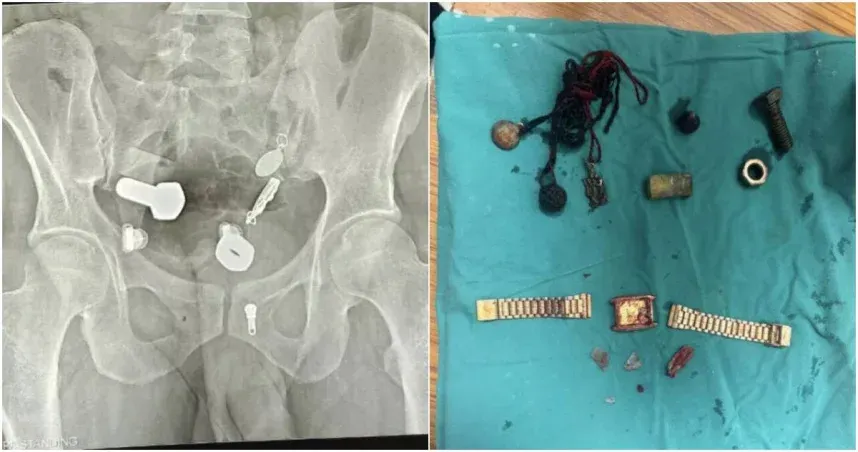

ชายหนุ่มปวดท้องเข้าโรงพยาบาล พบนาฬิกาและสกรูพันกันอยู่ภายในร่างกาย คล้ายกับร้านขายฮาร์ดแวร์

เมื่อไม่นานมานี้ ชายคนหนึ่งในอินเดียเข้ารับการรักษาตัวจากอาการปวดท้องอย่างรุนแรงจนทำให้รับประทานอาหารลำบาก ในตอนแรกแพทย์สงสัยว่าอาจเป็นปัญหาระบบย่อยอาหารทั่วไป แต่การเอกซเรย์เผยให้เห็นวัตถุแปลกประหลาดหลายอย่างอยู่ภายในร่างกายของเขา รวมถึงนาฬิกา น็อต สลักเกลียว และเศษโลหะจำนวนมาก การผ่าตัดใช้เวลาสามชั่วโมงจึงสามารถกำจัดเศษโลหะทั้งหมดได้สำเร็จ

ตามรายงานของ Mirror เหตุการณ์นี้เกิดขึ้นที่โรงพยาบาล Sawai Mansingh ในเมืองชัยปุระ ประเทศอินเดีย ผู้ป่วยซึ่งครอบครัวรีบนำตัวส่งโรงพยาบาลอย่างเร่งด่วน มีอาการปวดท้องและร่างกายอ่อนแรงอย่างรุนแรงเนื่องจากไม่สามารถรับประทานอาหารหรือดื่มน้ำได้ การสแกนเอกซเรย์เผยให้เห็นนาฬิกาฝังแน่นอยู่ในหลอดอาหาร และมีเศษโลหะ น็อต สลักเกลียว และสิ่งของอื่นๆ จำนวนมากสะสมอยู่ในลำไส้ใหญ่ และกระจัดกระจายอยู่ทั่วไป ราวกับร้านขายอุปกรณ์ฮาร์ดแวร์ ก่อให้เกิดภัยคุกคามร้ายแรงต่อชีวิตของผู้ป่วย

แพทย์พยายามใช้การผ่าตัดผ่านกล้องเป็นครั้งแรก โดยหวังว่าจะนำสิ่งแปลกปลอมโลหะเหล่านี้ออกจากร่างกายผู้ป่วยโดยตรง แต่เนื่องจากสิ่งแปลกปลอมมีขนาดใหญ่และมีจำนวนมาก ความเสี่ยงและความยากของการผ่าตัดผ่านกล้องจึงสูงมาก และท้ายที่สุดก็ไม่สามารถเอาออกได้สำเร็จ

เนื่องจากไม่มีทางเลือกอื่น ทีมแพทย์จึงได้ผ่าตัดช่องท้องเล็กๆ ของชายคนนี้ และใช้เวลาสามชั่วโมงค่อยๆ นำสิ่งแปลกปลอมออกทีละชิ้น โชคดีที่ชายคนนี้ฟื้นตัวได้ดีหลังการผ่าตัด

ทีมแพทย์ยังพบว่าชายคนดังกล่าวมีนิสัยแปลกประหลาดในการกลืนสิ่งแปลกปลอม ครอบครัวของเขายังเปิดเผยว่าเขามีอาการอารมณ์แปรปรวนอย่างรุนแรงและมีพฤติกรรมที่แปรปรวนมากขึ้นในช่วงเดือนที่ผ่านมา จากประวัติทางการแพทย์ แพทย์ระบุว่าอาการของชายคนนี้จัดอยู่ในกลุ่มอาการที่พบได้บ่อยทางคลินิกที่เรียกว่า "Pica" ซึ่งเป็นอาการประสาทหลอนและควบคุมแรงกระตุ้นผิดปกติที่เกิดจากความเจ็บป่วยทางจิต การฟื้นตัวจำเป็นต้องได้รับคำปรึกษาทางจิตวิทยาและการใช้ยา มิฉะนั้น ผู้ป่วยมีแนวโน้มที่จะกลืนวัตถุอันตรายซ้ำๆ ทำให้เกิดความเสียหายที่ไม่สามารถรักษาให้หายได้